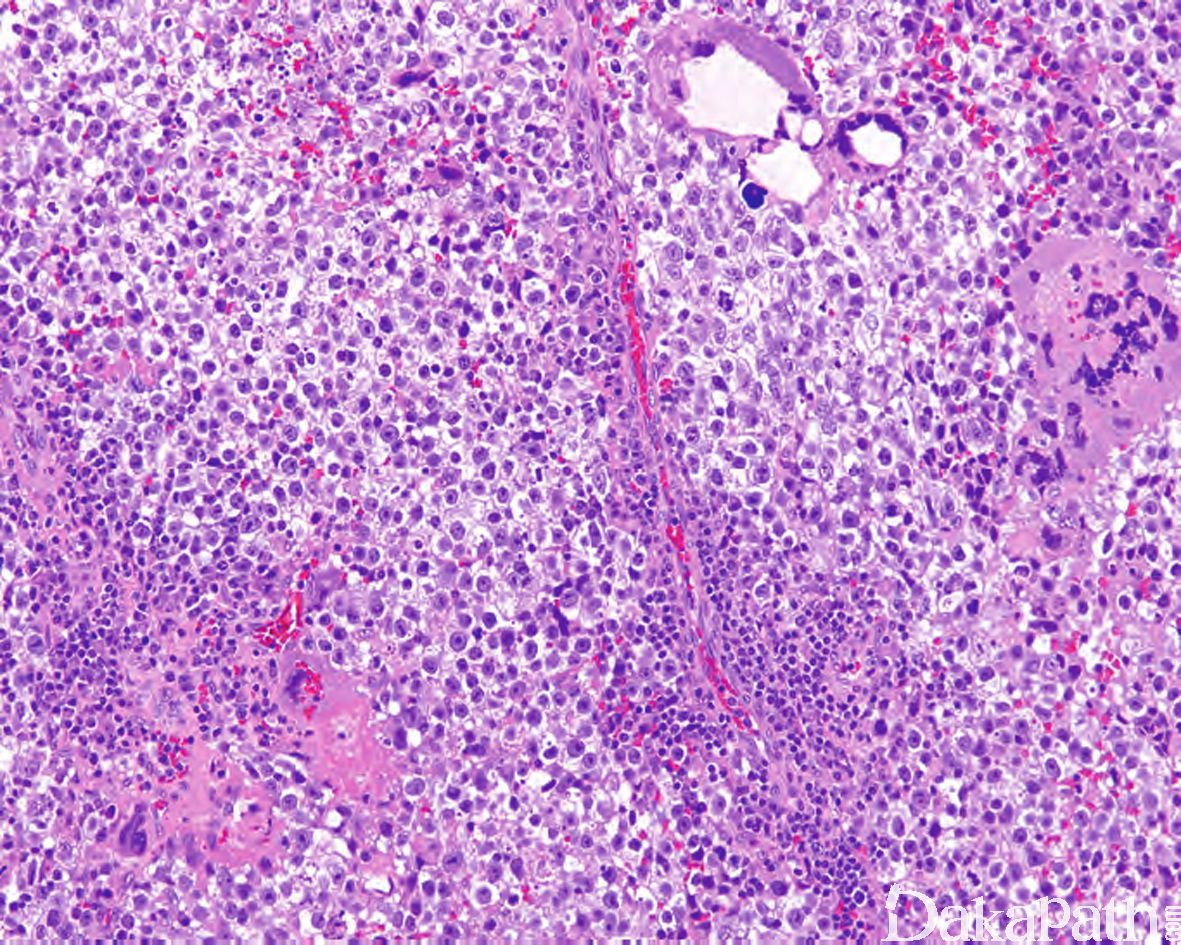

Testicular Seminoma With Syncytiotrophoblastic Cells

1.10-20%的精原细胞瘤可见多少不等的合体滋养层细胞,可广泛散在分布,也可显著聚集分布;血清 HCG 通常< 500u/L

典型的合体滋养层细胞通常具多个核,胞质丰富,致密嗜酸性合体状,可见胞质内空泡或陷窝;当多个合体滋养层细胞簇状聚集时,常伴有血湖形成;有时合体滋养层细胞仅有 1-2 个浓染的核在 HE 切片下不易认识,但其与经典的合体滋养层细胞的胞浆相似,可通过 HCG 的免疫组化染色识别;

无细胞滋养层细胞。

合体滋养层细胞 hCG 阳性。